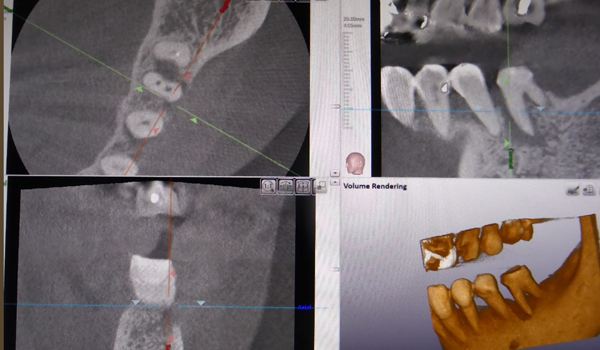

歯の根の治療時にCTを撮影することがあります。

何か月も治療が長引くケースの原因究明のためや、曲がった根の治療を行うときに根の長さや向きを調べるなど、様々な状況で利用します。

根のために使用するCTは細かいところまで映る必要があります。 よってインプラント治療を主に診断することを目的に作られたCTや医科用CTでは根の治療時に診断するのに利用するのは難しく、高性能の歯科用CTが必須となります。